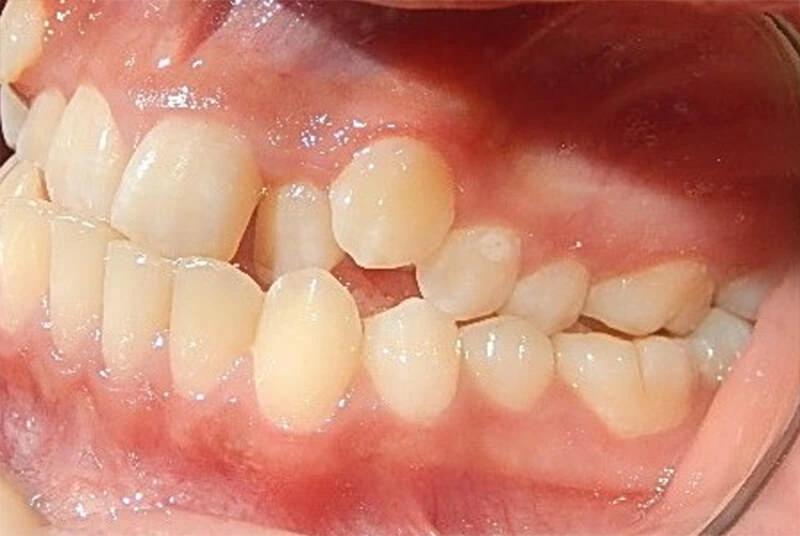

- En la mordida cruzada anterior, los incisivos superiores ocluyen por dentro de los inferiores, mientras que en la sobremordida, los dientes superiores cubren excesivamente a los inferiores.

Casos de clase III esquelética y corrección quirúrgica

En los casos de clase III esquelética, donde existe una discrepancia significativa entre los maxilares, la cirugía puede ser necesaria para reposicionar los huesos.

Este tipo de tratamiento requiere un enfoque multidisciplinario, involucrando tanto a ortodoncistas como a cirujanos maxilofaciales para asegurar una corrección precisa y efectiva.